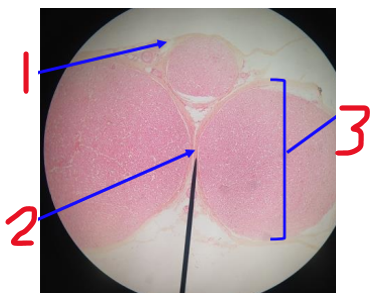

Name 1 (outer layer)

epineurium

Name 2

perineurium

Name 3

nerve fascicle

What is this a cross section of?

nerve